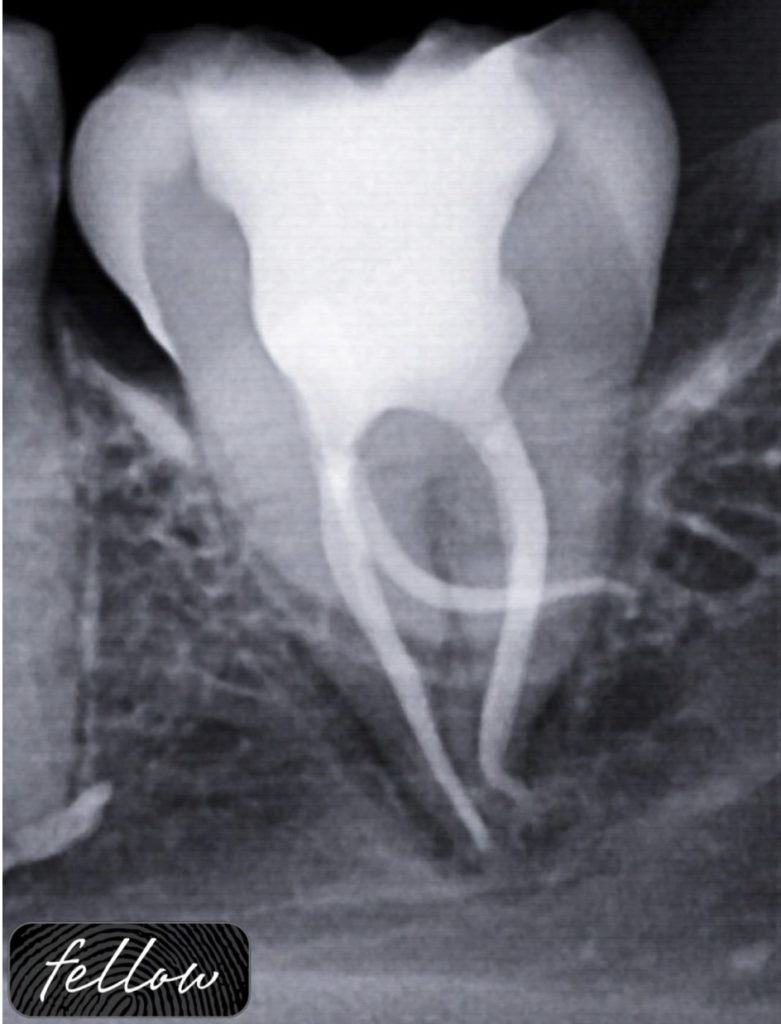

Dealing with severely curved canals in lower molar

Managing severely curved canals in endodontics requires careful planning and technique to prevent complications such as ledging, transportation, or instrument separation. Preoperative radiographs and CBCT imaging help assess curvature severity. Glide path creation is crucial, often using small, flexible hand files (e.g., #08 or #10 K-files) with a watch-winding motion. Nickel-titanium rotary or reciprocating instruments with enhanced flexibility, such as heat-treated files, are preferred for shaping. Frequent irrigation with sodium hypochlorite and activation of irrigation aid in smooth instrumentation. Passive step-back or crown-down techniques help reduce stress on files. Gentle, controlled movements and regular recapitulation minimize procedural errors. In cases of extreme curvature, hybrid approaches combining hand and rotary instrumentation may be employed starting with cronal flaring. Ultimately, successful management of curved canals relies on patience, tactile control, and adherence to established protocols.

Fig. 1